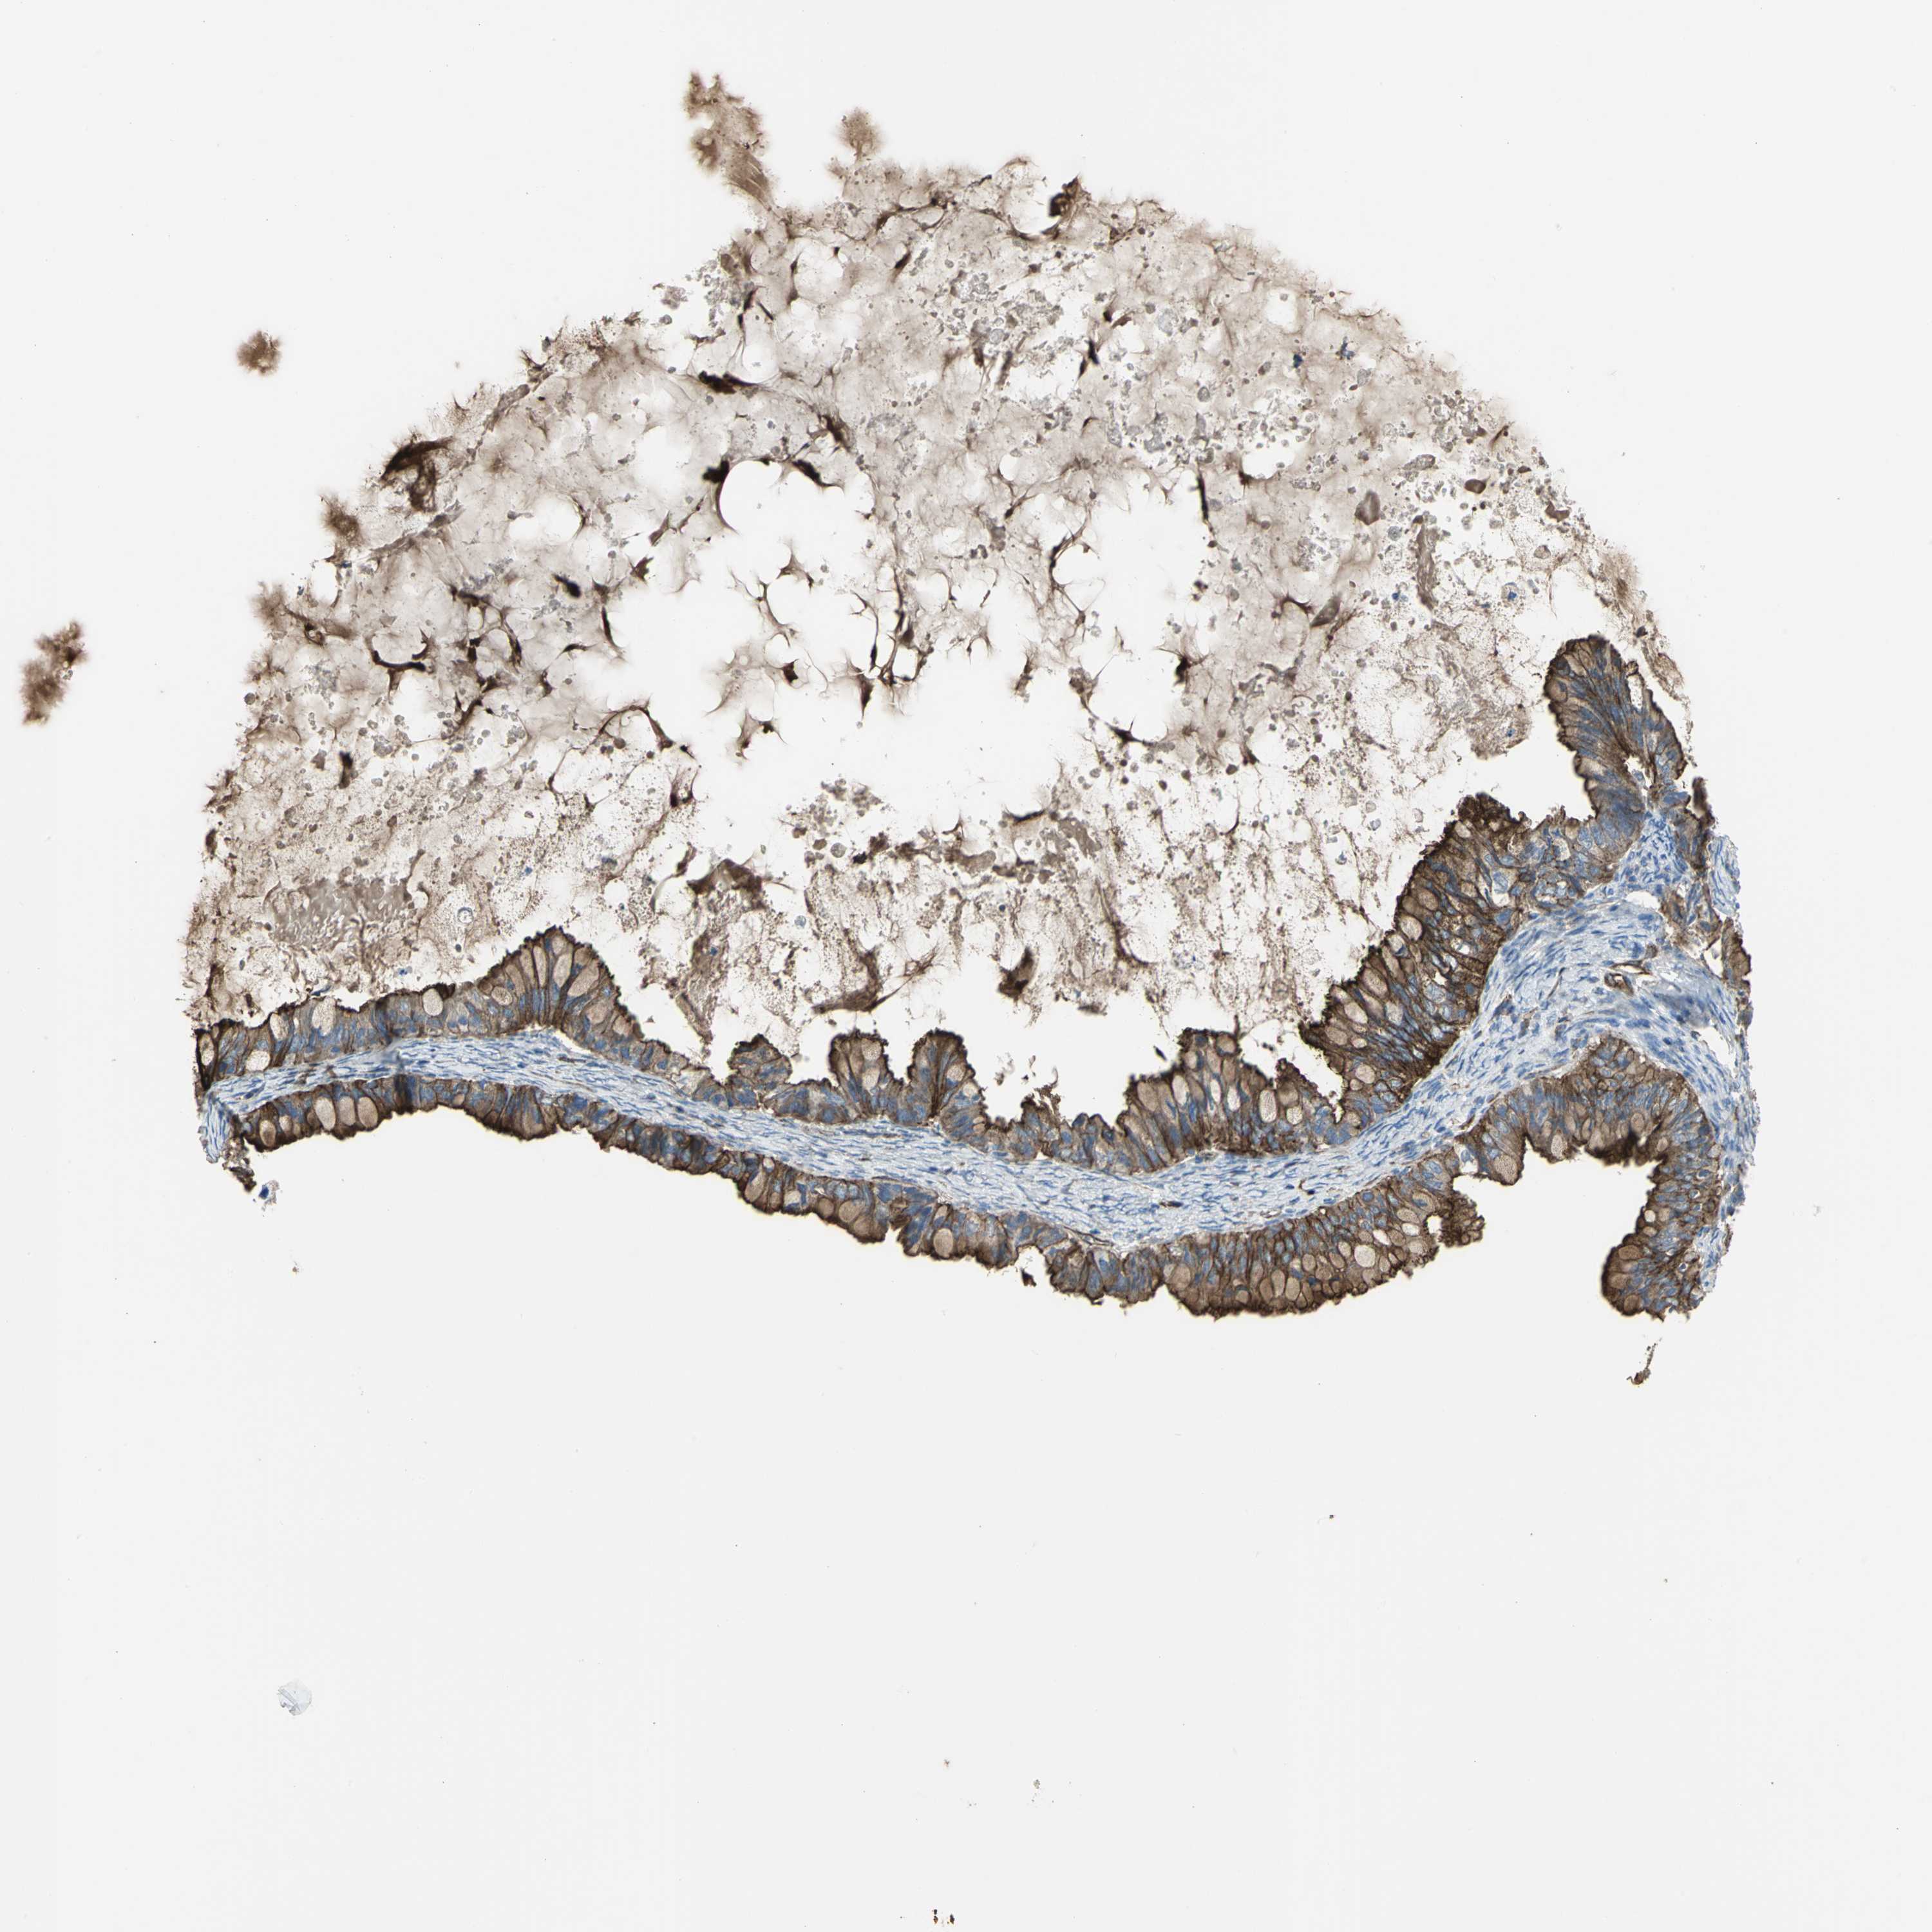

OVARIAN CANCER - Protein expressioni

A mouse-over function shows sample information and annotation data. Click on an image to view it in a full screen mode. Samples can be filtered based on level of antibody staining by selecting one or several of the following categories: high, medium, low and not detected. The assay and annotation is described here.

Note that samples used for immunohistochemistry by the Human Protein Atlas do not correspond to samples in the TCGA dataset.

Antibody stainingi

Antibody staining in the annotated cell types in the current human tissue is reported as not detected, low, medium, or high, based on conventional immunohistochemistry profiling in selected tissues. This score is based on the combination of the staining intensity and fraction of stained cells.

Each image is clickable and will lead to virtual microscopy that enables deeper exploration of all samples and also displays staining intensity scores, fraction scores and subcellular localization as well as patient and tissue information for each sample.

Antibody HPA004747

Antibody HPA004886

Antibody CAB019322

Cystadenocarcinoma, serous, NOS

Carcinoma, endometroid

Carcinoma, NOS

Cystadenocarcinoma, mucinous, NOS